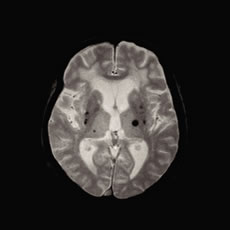

![]() |

| 図2)MRIの画像。脳内に黒い点状の所見(脳内出血の痕)を多数認める |

脳卒中は、特に高血圧が大きな要因です。高血圧を放置している方の脳のMRIでは、微小脳出血という小さな脳内出血の痕をたくさん認めることがあります(図2)。 これは脳内の細い動脈の動脈硬化が進行して、血液が漏れ出したものです。このような症状の方は近い将来、脳出血や脳梗塞になる危険性が高いことがわかって います。また微小脳出血がたくさんあると認知症の原因になるとも言われています。高血圧以外に糖尿病や脂質異常症(高脂血症)もある方はさらに脳卒中を起 こす危険が高いので、しっかり治療することが大切です。